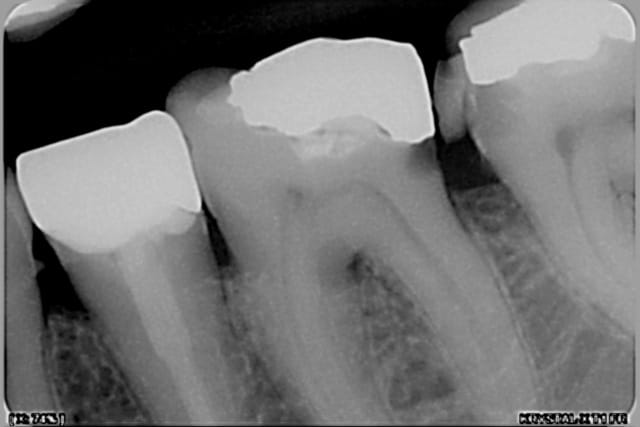

et deux exemples en radios de cas similaires, un peu plus sous gingivaux d'ailleurs

Pr  op 2 copy ydqcpc - Eugenol

Post op 3 copy yxqhog - Eugenol